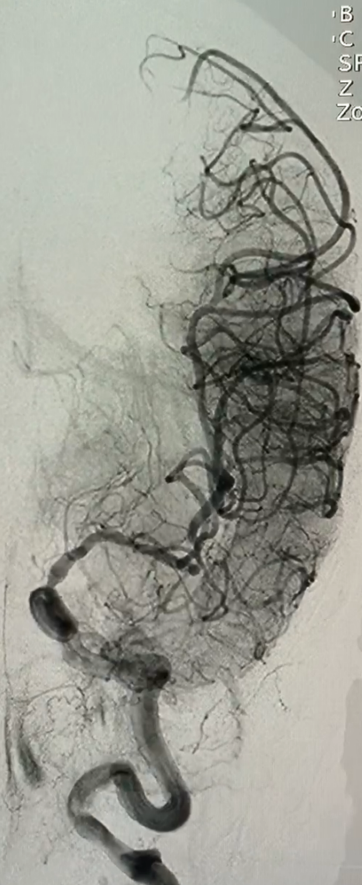

Mạch máu đã thông và huyết khối lấy ra từ mạch máu não

Với sự hỗ trợ của máy chụp X-quang số hóa xóa nền, thạc sĩ-bác sỹ Phùng Hưng và các cộng sự đã mở đường vào lòng mạch máu của người bệnh, đặt sheat 5F vào động mạch đùi phải theo phương pháp Seldinger, luồn verteral catheter 5F + radifocus guidewire 0.035” vào động mạch cảnh chung trái rồi đặt neuron max 088 đến gốc động mạch cảnh chung trái, đưa sofia plus đến đoạn động mạch cảnh chung bị tắc để hút huyết khối, đặt PX-SLIM và wire sion 0.014 lên động mạch cảnh trong trái nội sọ kéo ra nhiều huyết khối đen. Sau can thiệp, động mạch cảnh trong não giữa trái của người bệnh thông hoàn toàn, tưới máu nội sọ trái TICI 2b, động mạch cảnh trong phải ưu thế, bàng hệ não trước trái. Đến ngày thứ 3 sau phẫu thuật, cụ bà Đặng Thị Thể đã hồi phục phần lớn các chức năng vận động, có sự nhận biết khi được gọi hỏi, cử động được và có cảm giác ở tay chân bên trái.